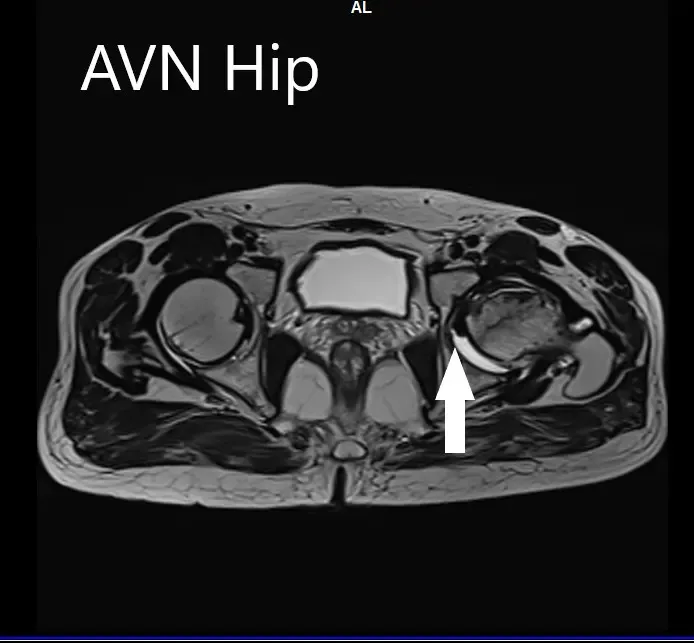

An MRI was obtained for diagnostic confirmation and staging of the disease. The left femoral head was collapsed with irregular contour and showed areas of altered signal intensity with a line of demarcation. Hypointense areas both on T1WI & T2WI seen in head suggestive of sclerosis. Surrounding marrow edema was seen

The left hip had advanced avascular necrosis with a collapse. The right hip was uninvolved presently. He was educated about the worsening collapse of the hip joint leading to his symptoms. Although the patient was young, he was advised a total hip replacement surgery in view of the collapse of the head of the femur with arthritis.